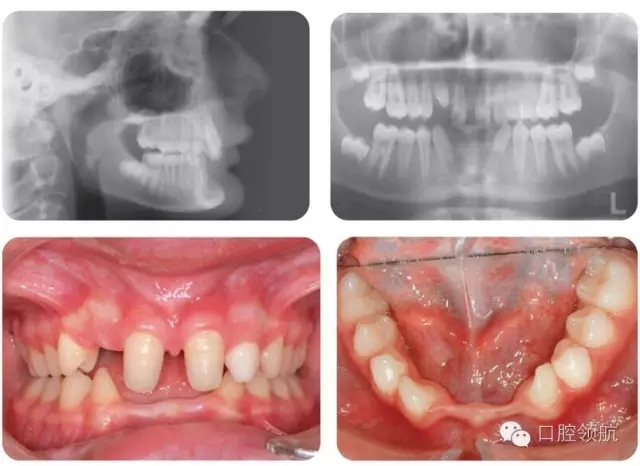

這個(gè)時(shí)期矯正反的優(yōu)勢(shì)有哪些?

● 可以去除任何下頜骨的錯(cuò)位

● 避免LR1發(fā)生牙齦退縮。

● 正常覆有利于咬合穩(wěn)定。

該病例正畸治療需求指數(shù)(IOTN)是什么?

取決于下頜在后退接觸位(RCP)和牙尖交錯(cuò)位(ICP)時(shí)移動(dòng)的距離。該病例中大于2mm,提示IOTN為4.c. 如果在1~2mm之間,IOTN為3.c, 小于1mm為2.c.

怎樣治療該病例?

使用活動(dòng)矯治器唇傾UR1,糾正反。也可以采用2x4固定矯治器,但UR2的位置使矯治難度加大。

怎樣設(shè)計(jì)活動(dòng)矯治器?

● 固位體可在UR6、URD和ULD、UL6設(shè)計(jì)箭頭卡環(huán)(或者UR6、URE和URE和UL6設(shè)計(jì)雙臂卡)(0.7mm的不銹鋼絲)。

● Z型簧(0.5mm不銹鋼絲)推UR1唇傾。

● 覆蓋后牙的板(打開(kāi)咬合,使UR1移動(dòng))。